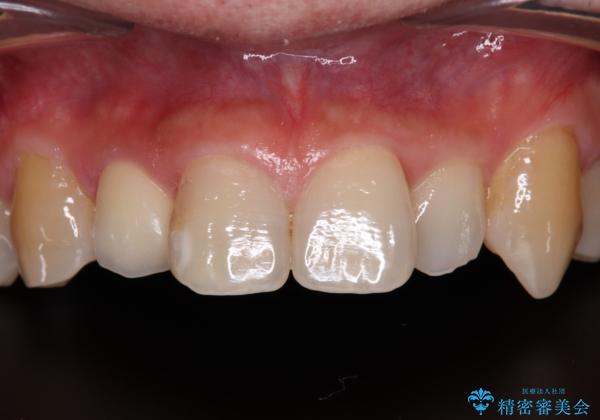

擦れてしみる前歯 オールセラミッククラウンで痛みを改善

内側に倒れているため、下顎と強く干渉することが懸念されましたが、無理のない咬み合わせで、形態も左右対称に近い状態で仕上げることができました。